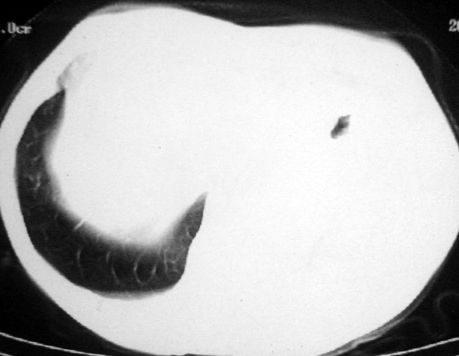

男,54岁,咳嗽,气喘半年,胸痛一月.

血性胸水

左侧胸腔积液 斜裂积液 心包积液 左肺不张 考虑左肺ca并胸膜心包转移。

支持左肺下叶中心型肺癌(累及舌叶)伴阻塞性肺炎、膨胀不全、胸腔积液、心包少量积液。

考虑左肺下叶中央型肺癌伴阻塞性肺炎及肺不张,纵隔受累可能,胸膜转移。